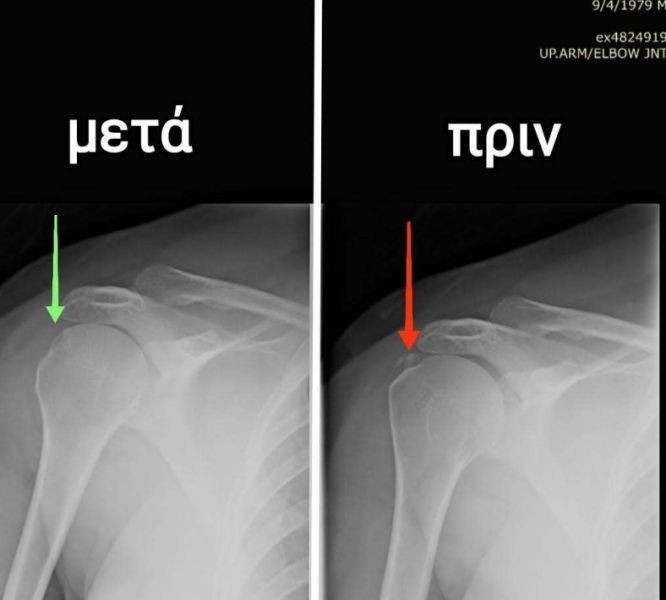

Διάλυση ασβεστώματος ώμου